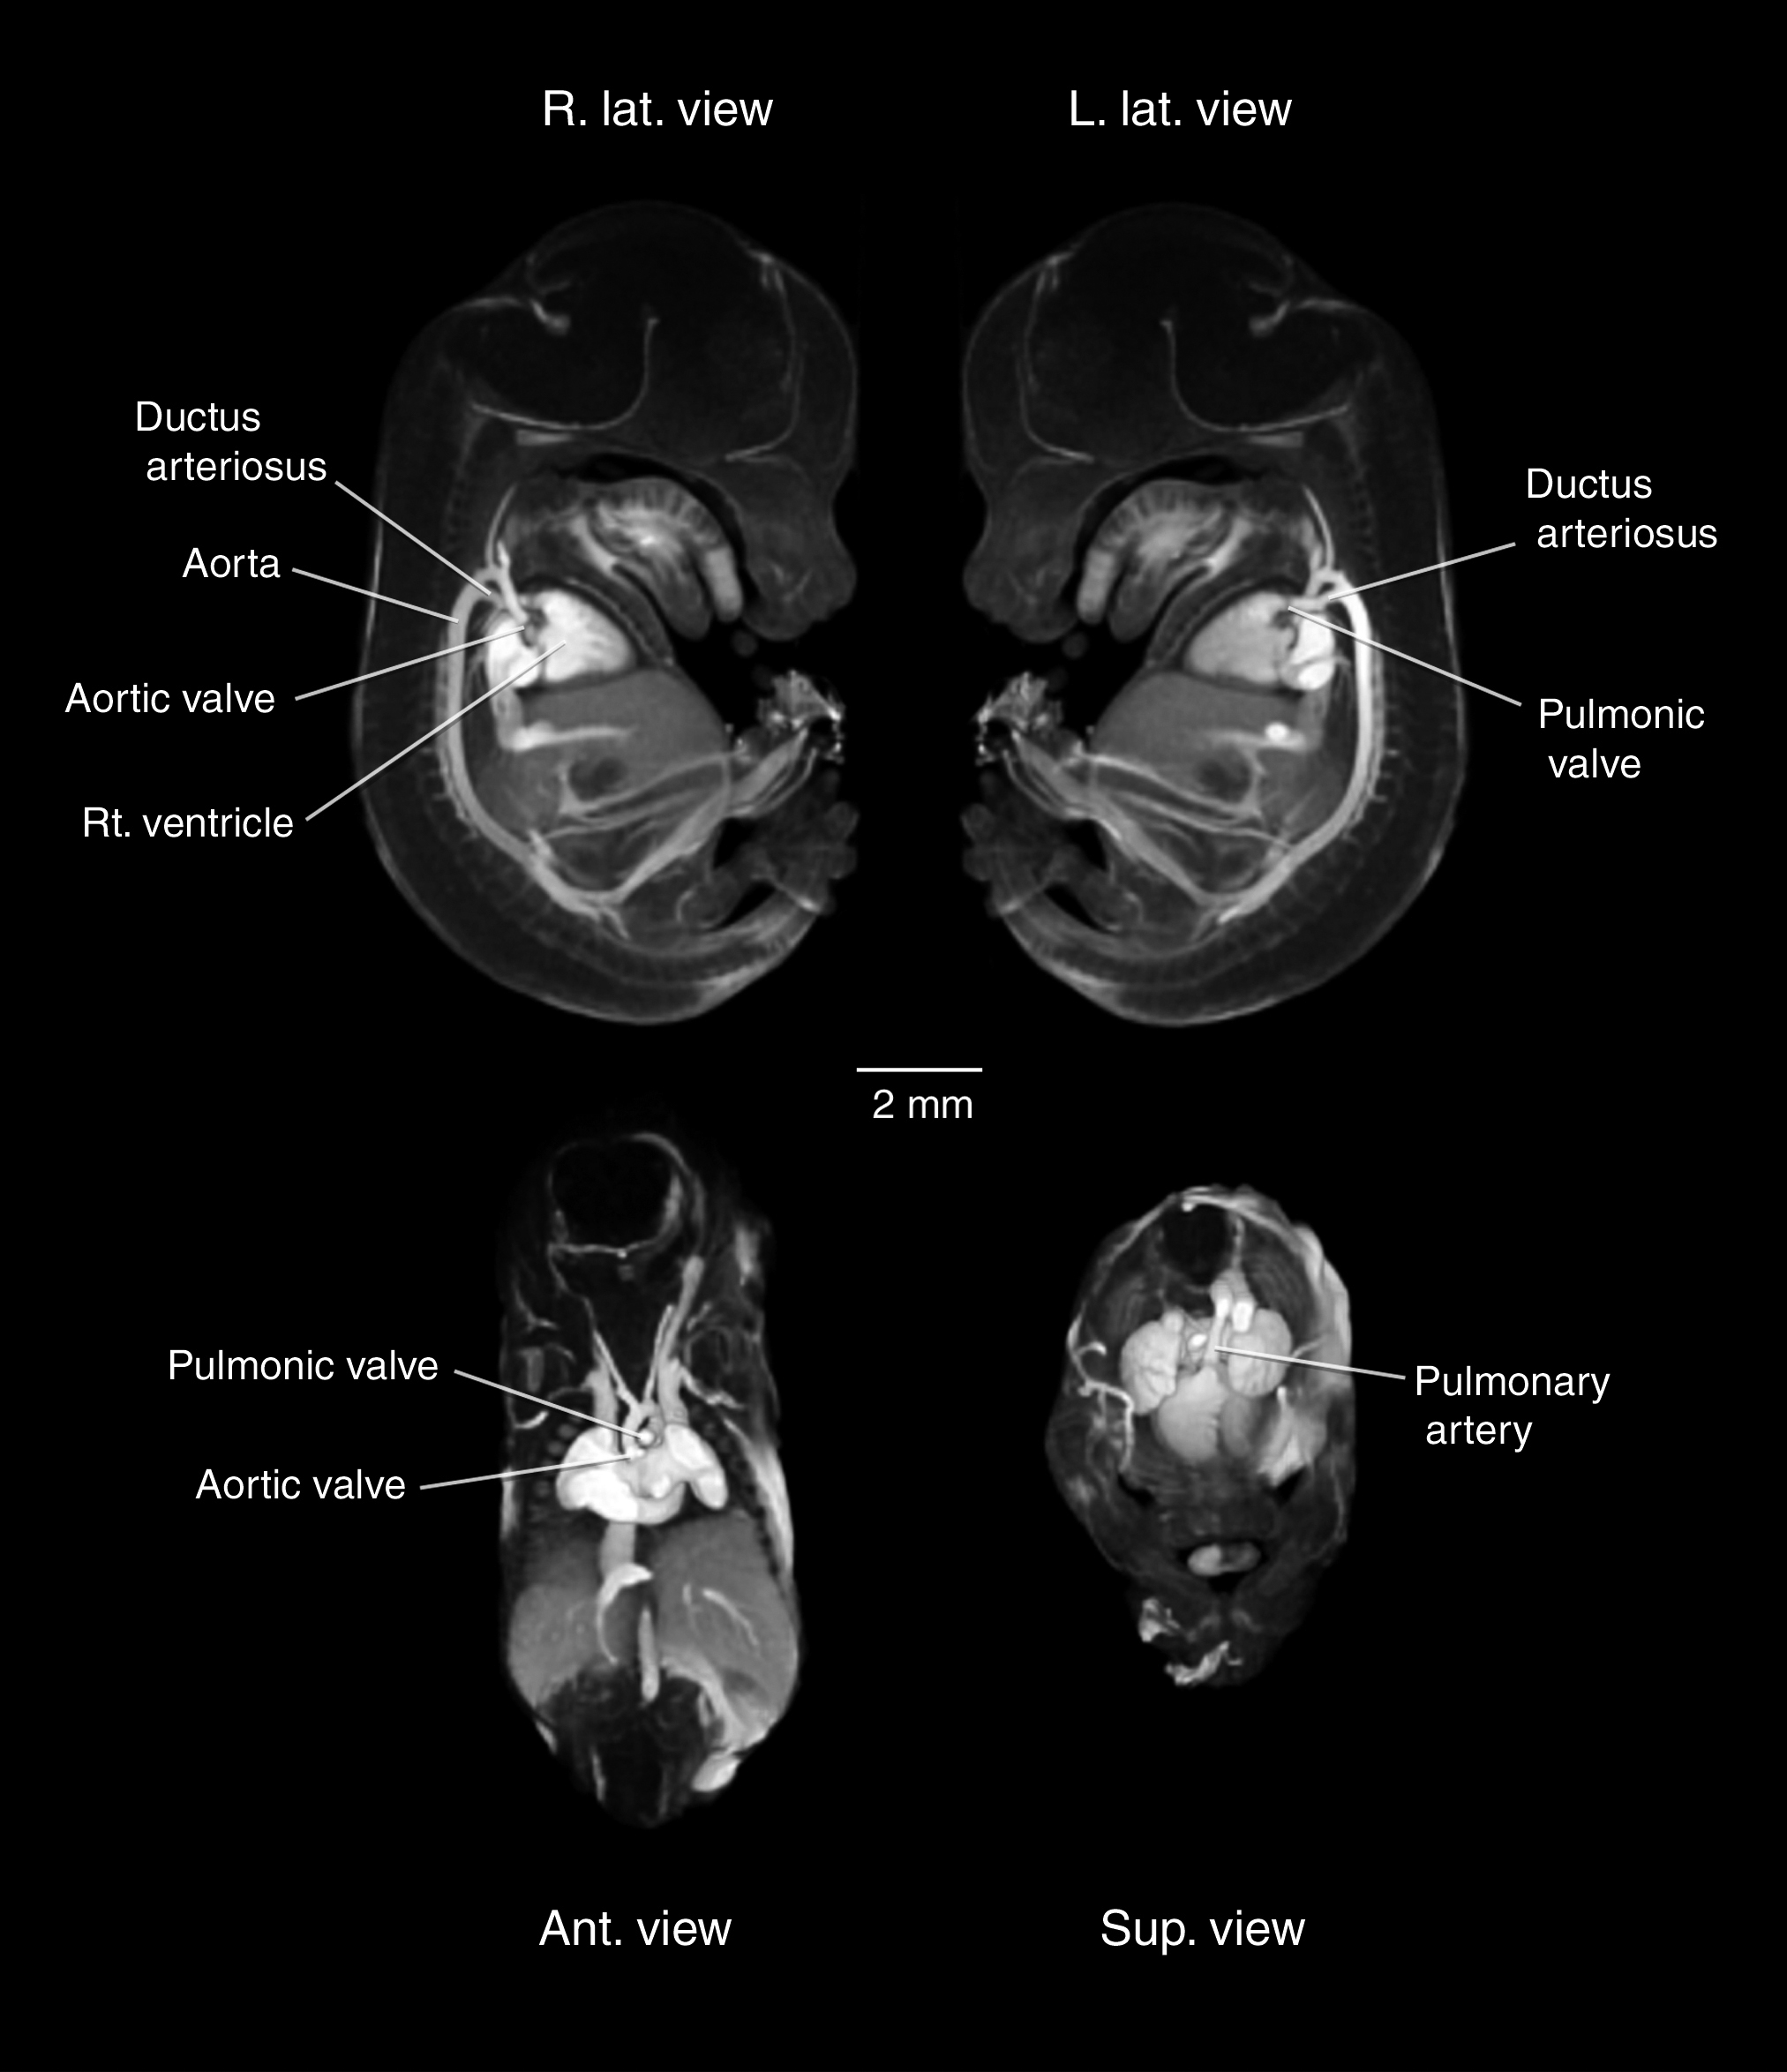

Magnetic Resonance Angiography

(MRA)

MRA Volume Renderings

MRA Animations